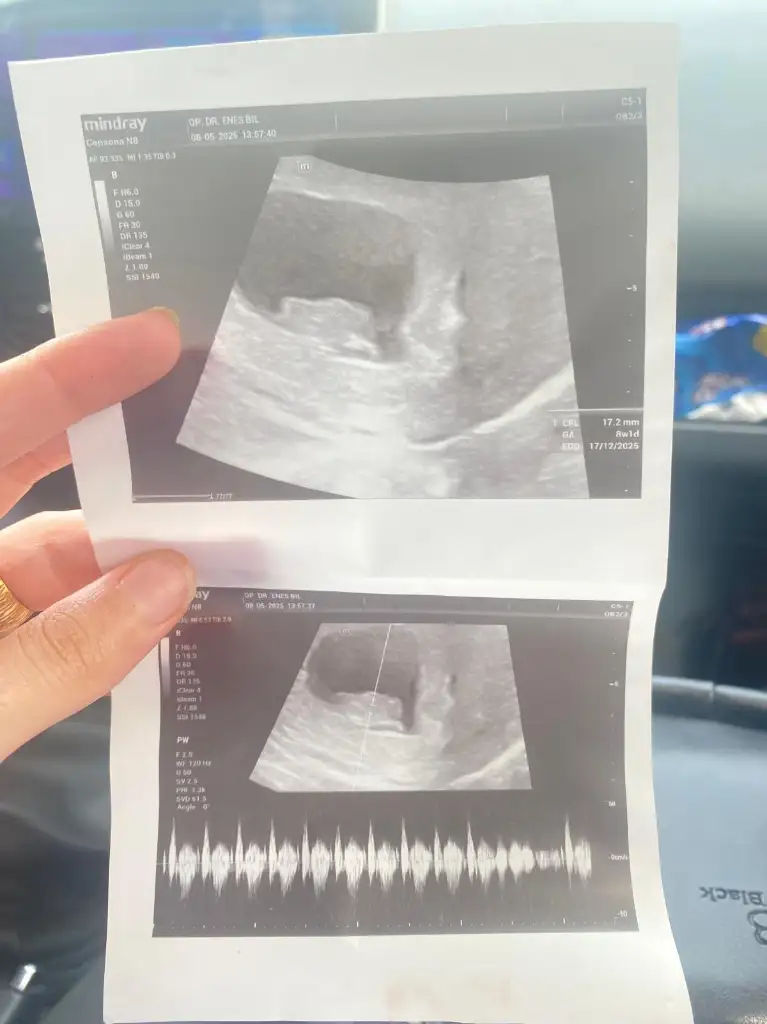

Merhaba 8+2 vajinal muayene sizce cinsiyeti nedir

Merhaba buda arkadaşımın 8 haftalık tahmin yapabilirmisinizErkek olduğunu düşünüyorum

Buda 8 haftalık heErkek olduğunu düşünüyorum